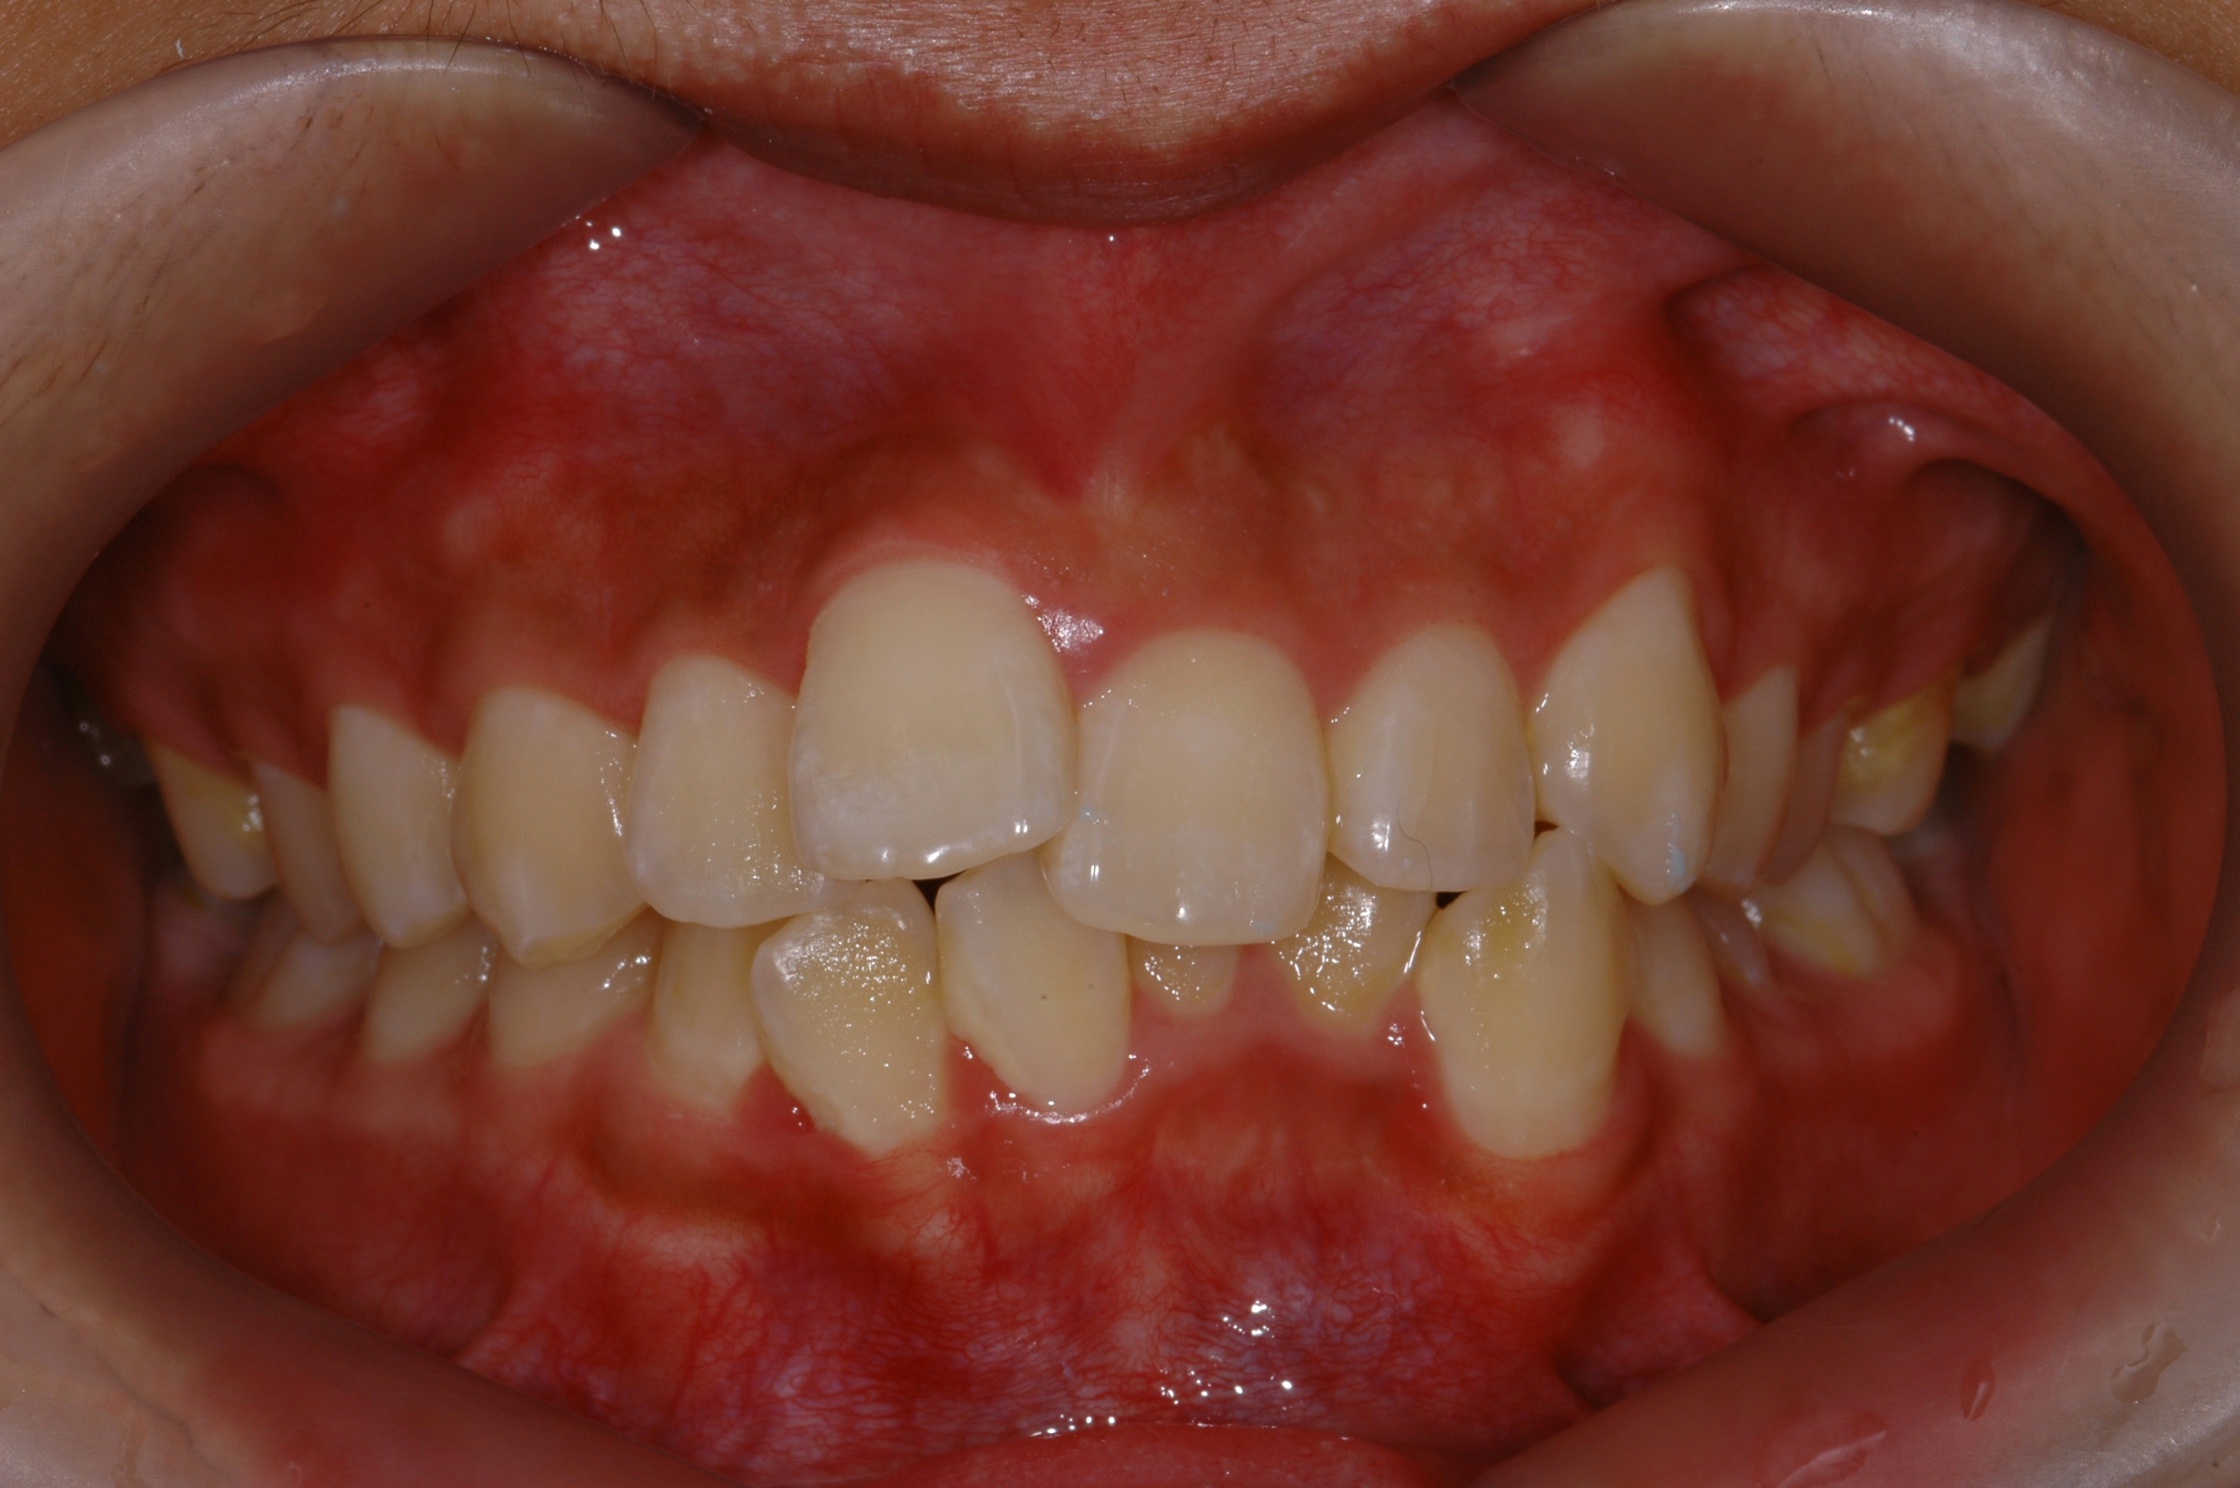

치료 전 사진입니다.